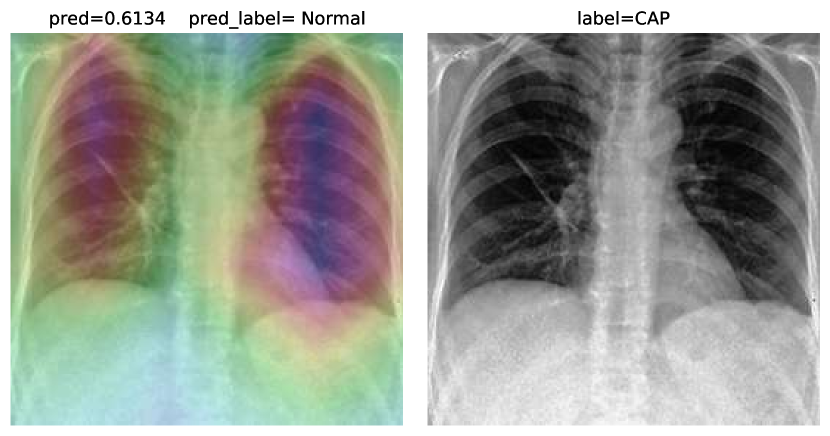

While text removal methods can prevent overfitting, we can simply force the model to look into the lungs in order to address both problems in one effort. To accomplish this task, a U-Net based segmentation illustrated in Fig. 4 is applied to the input images before enhancements. Visualization results for COVID-CXNet with the ROI-segmentation block are shown in Fig. 18.

Refer to caption

Figure 18: Grad-CAM visualization of the proposed model, trained with lung-segmented CXRs, over sample cases.

A figure with more Grad-CAMs is attached in Appendix B. From Fig. 18, it can be observed that COVID-CXNet with ROI-segmentation has delivered superior performance regarding the localization of pneumonia features. Worthwhile to mention that image augmentation is expanded by adding zoom-in, zoom-out, and brightness adjustment. Label smoothing is also applied to the loss function.

The proposed method has shown a negligible drop in metric scores; accuracy is decreased by 0.42%, and f-score is declined by 0.02. This decrease is a result of training with a larger dataset and accurately segmented ROIs, which means it has become more robust against unseen samples. There is a trade-off between catching good features and higher metric scores; while better features result in a more generalized model, high metric scores may indicate overfitting.